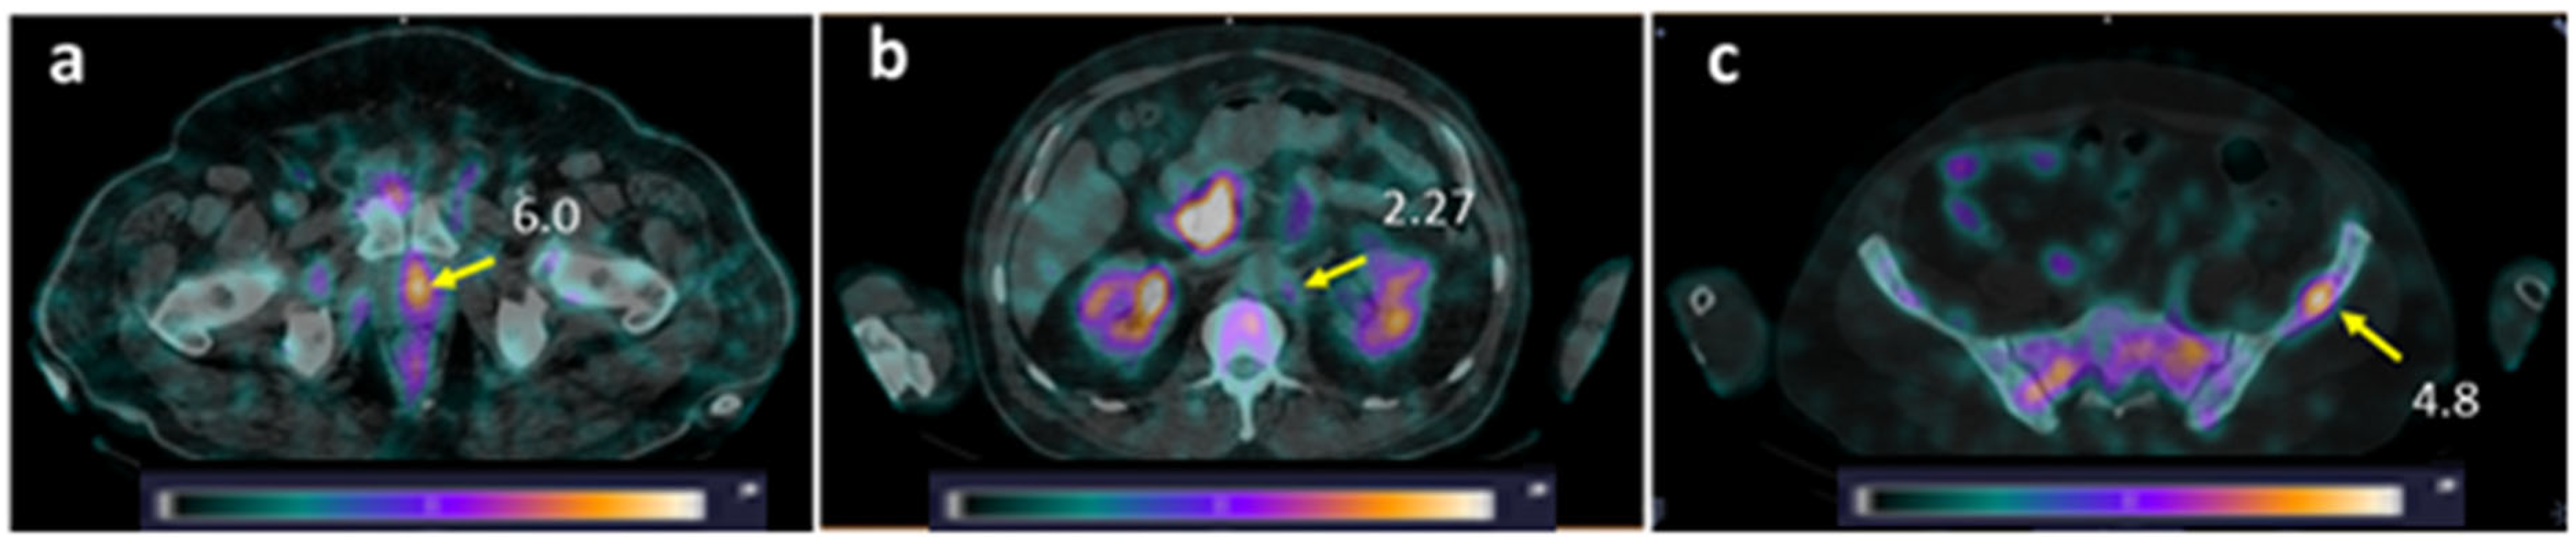

Figure 7. SPECT/CT images of PCa patients 2 h after injection of [99mTc]Tc-DB8. The foci of increased [99mTc]Tc-DB8 uptake (yellow arrow, SUVmax) are visualized (a) in the prostate (Patient 16); (b) in the paraaortic lymph node on the left (Patient 10); and (c) in the left ilium (Patient 10). A linear relative scale (normalized at the maximum activity in the image SUVmax from 0 to 5.0) is applied.

One patient (Patient 8, injected with a peptide mass of 80 µg) underwent SPECT visualization of PCa using the anti-PSMA targeting agent [99mTc]Tc-BQ0413 1 month before the current study (see Phase I study report [32], Patient 5). The comparison of GRPR SPECT and PSMA SPECT (Figure 8) revealed higher tumor uptake for [99mTc]Tc-DB8 in the primary lesion in the prostate gland. BM lesions were visualized with both agents; however, the contrast was higher for PSMA SPECT.